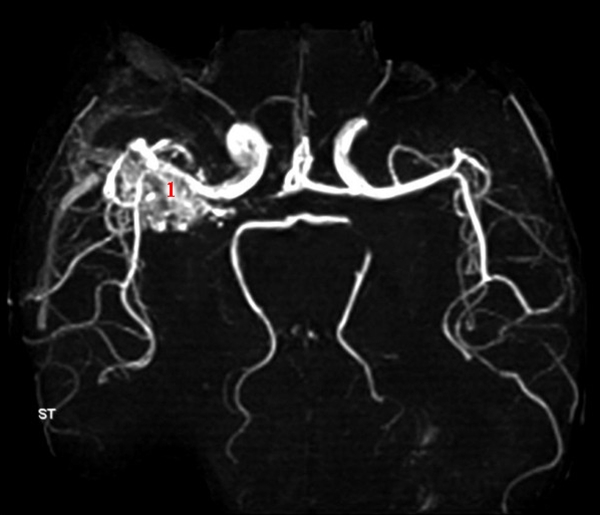

AV-malformation, MR angio

MR angio viser abnorm karnøgle (1) - en såkaldt AV-malformation.